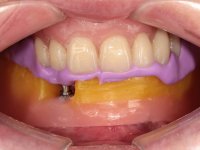

After clinical and radiological evaluation several rehabilitation plans were discussed with the patient. It was decided to extract the remaining lower teeth and do an overdenture retained by two dental implants with the locator attachement system to achieve a better retention and stabilization of the lower denture.

Two dental implants were planned in the CBCT scan, in the area of the inferior canines. The dental extractions were performed and, simultaneously, the alveolar crest was flattened and the implants were placed. Three issues were considered while implant placement: parallelism of the axis, same height of the implant’s neck, and same position in the coronal plan. This 3D insertion is essential to have a good retention of the overdenture in the future. Patient’s removable denture was fixed in the dental lab, to include the extracted teeth, and a soft-tissue relining was done over the healing abutments. After the osseo-integration period, a first impression was done with an open-tray and a doble-mix technique. This dental impression allowed the production of screwed wax-rims and an individual tray for a functional impression. A second impression, final, was done with an individual tray with a monophasic silicone. The occlusal wax-rims were correct in the mouth according to the full denture guidelines. Special care was taken with the occlusal vertical dimension and the support in the soft-tissues. A silicone bite registration material was used to better defined the intermaxillary relations. Teeth set-up was done in the dental lab with the selected tooth color. Due to the fact that the base was screwed to the dental implants, the teeth set-up was functionally evaluated in the mouth. Another silicone bite registration material was used to allow final occlusal adjustments. Finally, the locators were screwed and the retention nylons were selected according to the patient needs.